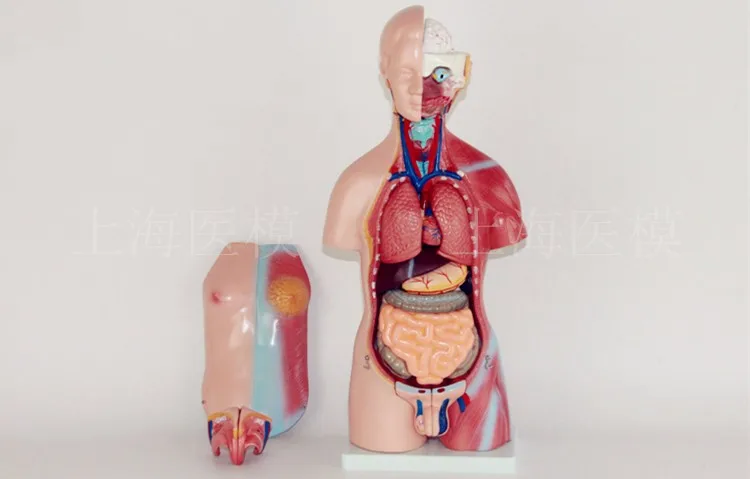

45CM uniex human Torso human anatomical structure model internal organ model 23 parts